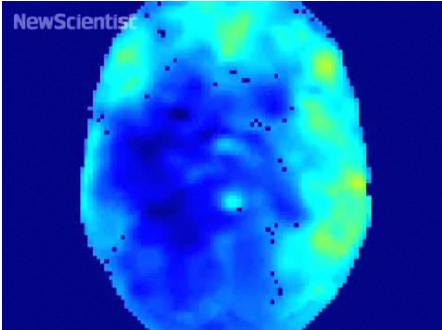

ABD'deki Hartford Üniversitesi'nden felsefe profesörü Dan Lloyd, MR görüntüleri ile müziği birleştiren bir bilgisayar programı tasarladı. Lloyd, bilgisayar oyunu oynarken, oyundaki manzarayı izlerken ve dinlenirken MR ile beyninin görüntülerini aldı.

Aynı zamanda etkin hale gelen bölgeleri belirleyen bilim adamı, bu bölgelerin her birine bir ton verdi. Sesin kuvveti bu bölgelerin faaliyet yoğunluğuyla bağlantılıydı.

Sonuç olarak, bilim adamının hareketlerinin değişmesiyle ilginç bir melodi ortaya çıktı.

Bununla da yetinmeyen Lloyd, aynı deneyi başka sağlıklı kişiler ve şizofreni hastaları üzerinde de yaptı. Şizofreni hastalarında müzikal değişimlerin daha belirgin olduğu görüldü.